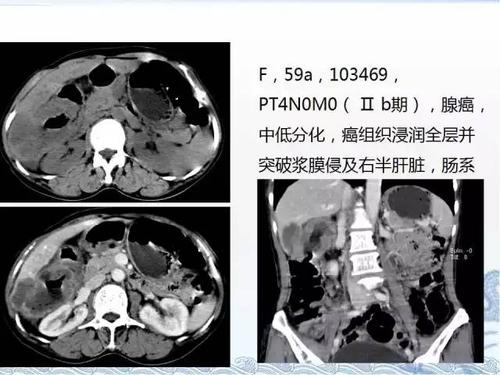

ct检查及诊断攻略——胃癌,结直肠癌

ct检查及诊断攻略胃癌结直肠癌